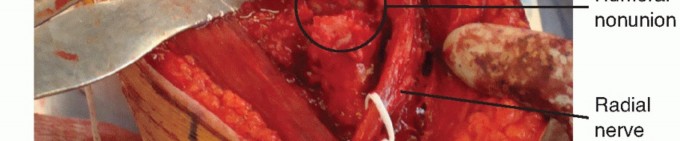

POSTERIOR APPROACH TO THE HUMERUS

Indications

ORIF of a fracture of the humerus Treatment of nonunion

Exploration of the radial nerve in the spiral groove

Incision

A longitudinal incision is made in the midline of the posterior aspect of the arm, from 8 cm below the acromion to the olecranon fossa (FIG 5A).

The spiral groove contains the radial nerve; the radial nerve separates the origins of the lateral and medial heads (FIG 5C*).

To avoid iatrogenic nerve injury, the surgeon should never continue dissection down to bone in the proximal two-thirds of the arm until the radial nerve has been identified.

FIG 5 • (continued) C. In this humeral shaft nonunion, the triceps is reflected medially and the radial nerve can be seen passing through the spiral groove. (A: Courtesy of Matthew J. Garberina, MD, and Charles L. Getz, MD.)*